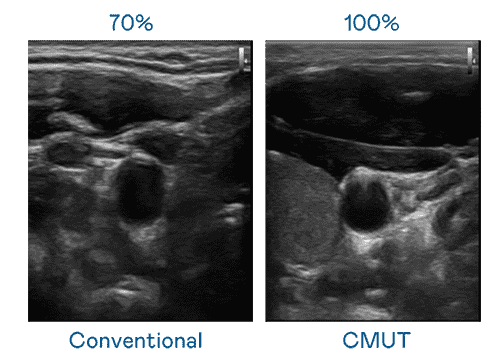

CMUT 技术是一种用电容式微机电元件来产生超音波讯号的技术。。。与传统 PZT 压电式技术相比,,,CMUT 频宽增加 30%,,,更宽频的超音波讯号让影像解析度大幅提升,,是实现高影像品质医疗超音波扫描、、、促进精准医疗发展的关键技术。。。。

大频宽带来超清晰影像

超音波影像的解析度高低,,,,首先取决于探头能发出的讯号频宽。。汇旺支付 CMUT 可提供高清晰的超音波讯号,,,提供高频宽、、、、高灵敏度、、影像纹理细节更高的超音波影像,,,协助医护人员缩短影像判读时间及利用精准的医疗影像进行诊断。。。。